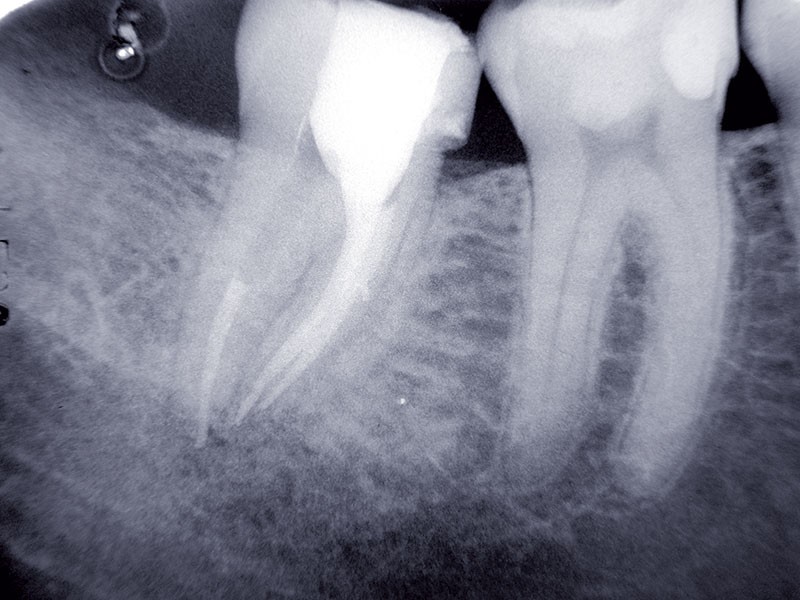

L’essentiel des litiges porte sur la prothèse (40 % de l’ensemble des déclarations). Leur nombre est en forte baisse de 15 %, avec 614 dossiers contre 722 en 2018. La prothèse conjointe (couronne, bridge, inlay, onlay) a fait l’objet de 470 déclarations (76 % du groupe prothèse) dont 169 relatives à des soins endodontiques préprothétiques non conformes (ou non repris) : perforation radiculaire (23 cas), bris instrumentaux (40), obturation canalaire non conforme (106), lésion apicale… À noter également, 194 litiges portant sur des restaurations techniquement inadaptées : insuffisance de point de contact, équilibration occlusale ou étanchéité périphérique, reprises de carie sous restauration, descellements… La prothèse adjointe concerne 116 déclarations (20 %) dont 65 dossiers portant sur la prothèses complète (résine ou stellite). Enfin la prothèse mixte (conjointe + adjointe) est en cause dans 28 déclarations (4 %).

C’est le deuxième groupe d’importance par le volume des déclarations (30,6 % des litiges hors implantologie) en hausse de 7 % sur un an. Les fractures d’instruments endodontiques sont au cœur de 225 dossiers (47 % de ce groupe). On trouve également 41 litiges concernant des complications d’anesthésie et d’extraction, 24 liés àl’effraction et lésion du sinus maxillaire(hors suite d’actes implantaires), 13 erreurs d’extraction, 9 contestation de la conformité d’actes de parodontologie ou encore 13 déclarations au titred’alvéolite ou de complication en cicatrisation. Même si le nombre de litiges en endondontie diminue légèrement à 37 % du nombre de toutes les réclamations traitées hors implantologie, après 40 % en 2018, ce domaine, « reste un des postes le plus à risque de réclamation », souligne le rapport.